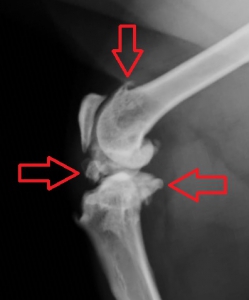

レントゲン検査では軟骨の評価が難しく、初期の病変を把握することは困難ですが、重症化するにつれて軟骨の付着している骨の部分が白っぽく硬化したり、骨棘(こつきょく)形成、炎症で増えた関節液による関節包の腫れなどが見られるようになります。

左下の写真がかなり重度の変形関節症を起こしている猫の膝関節のレントゲン写真です。赤い矢印で示したような関節症の進行に伴う関節鼠(ねずみ)(軟骨や骨のかけら)や骨棘(骨のでっぱり)が何か所も見られています。右が正常のものです。